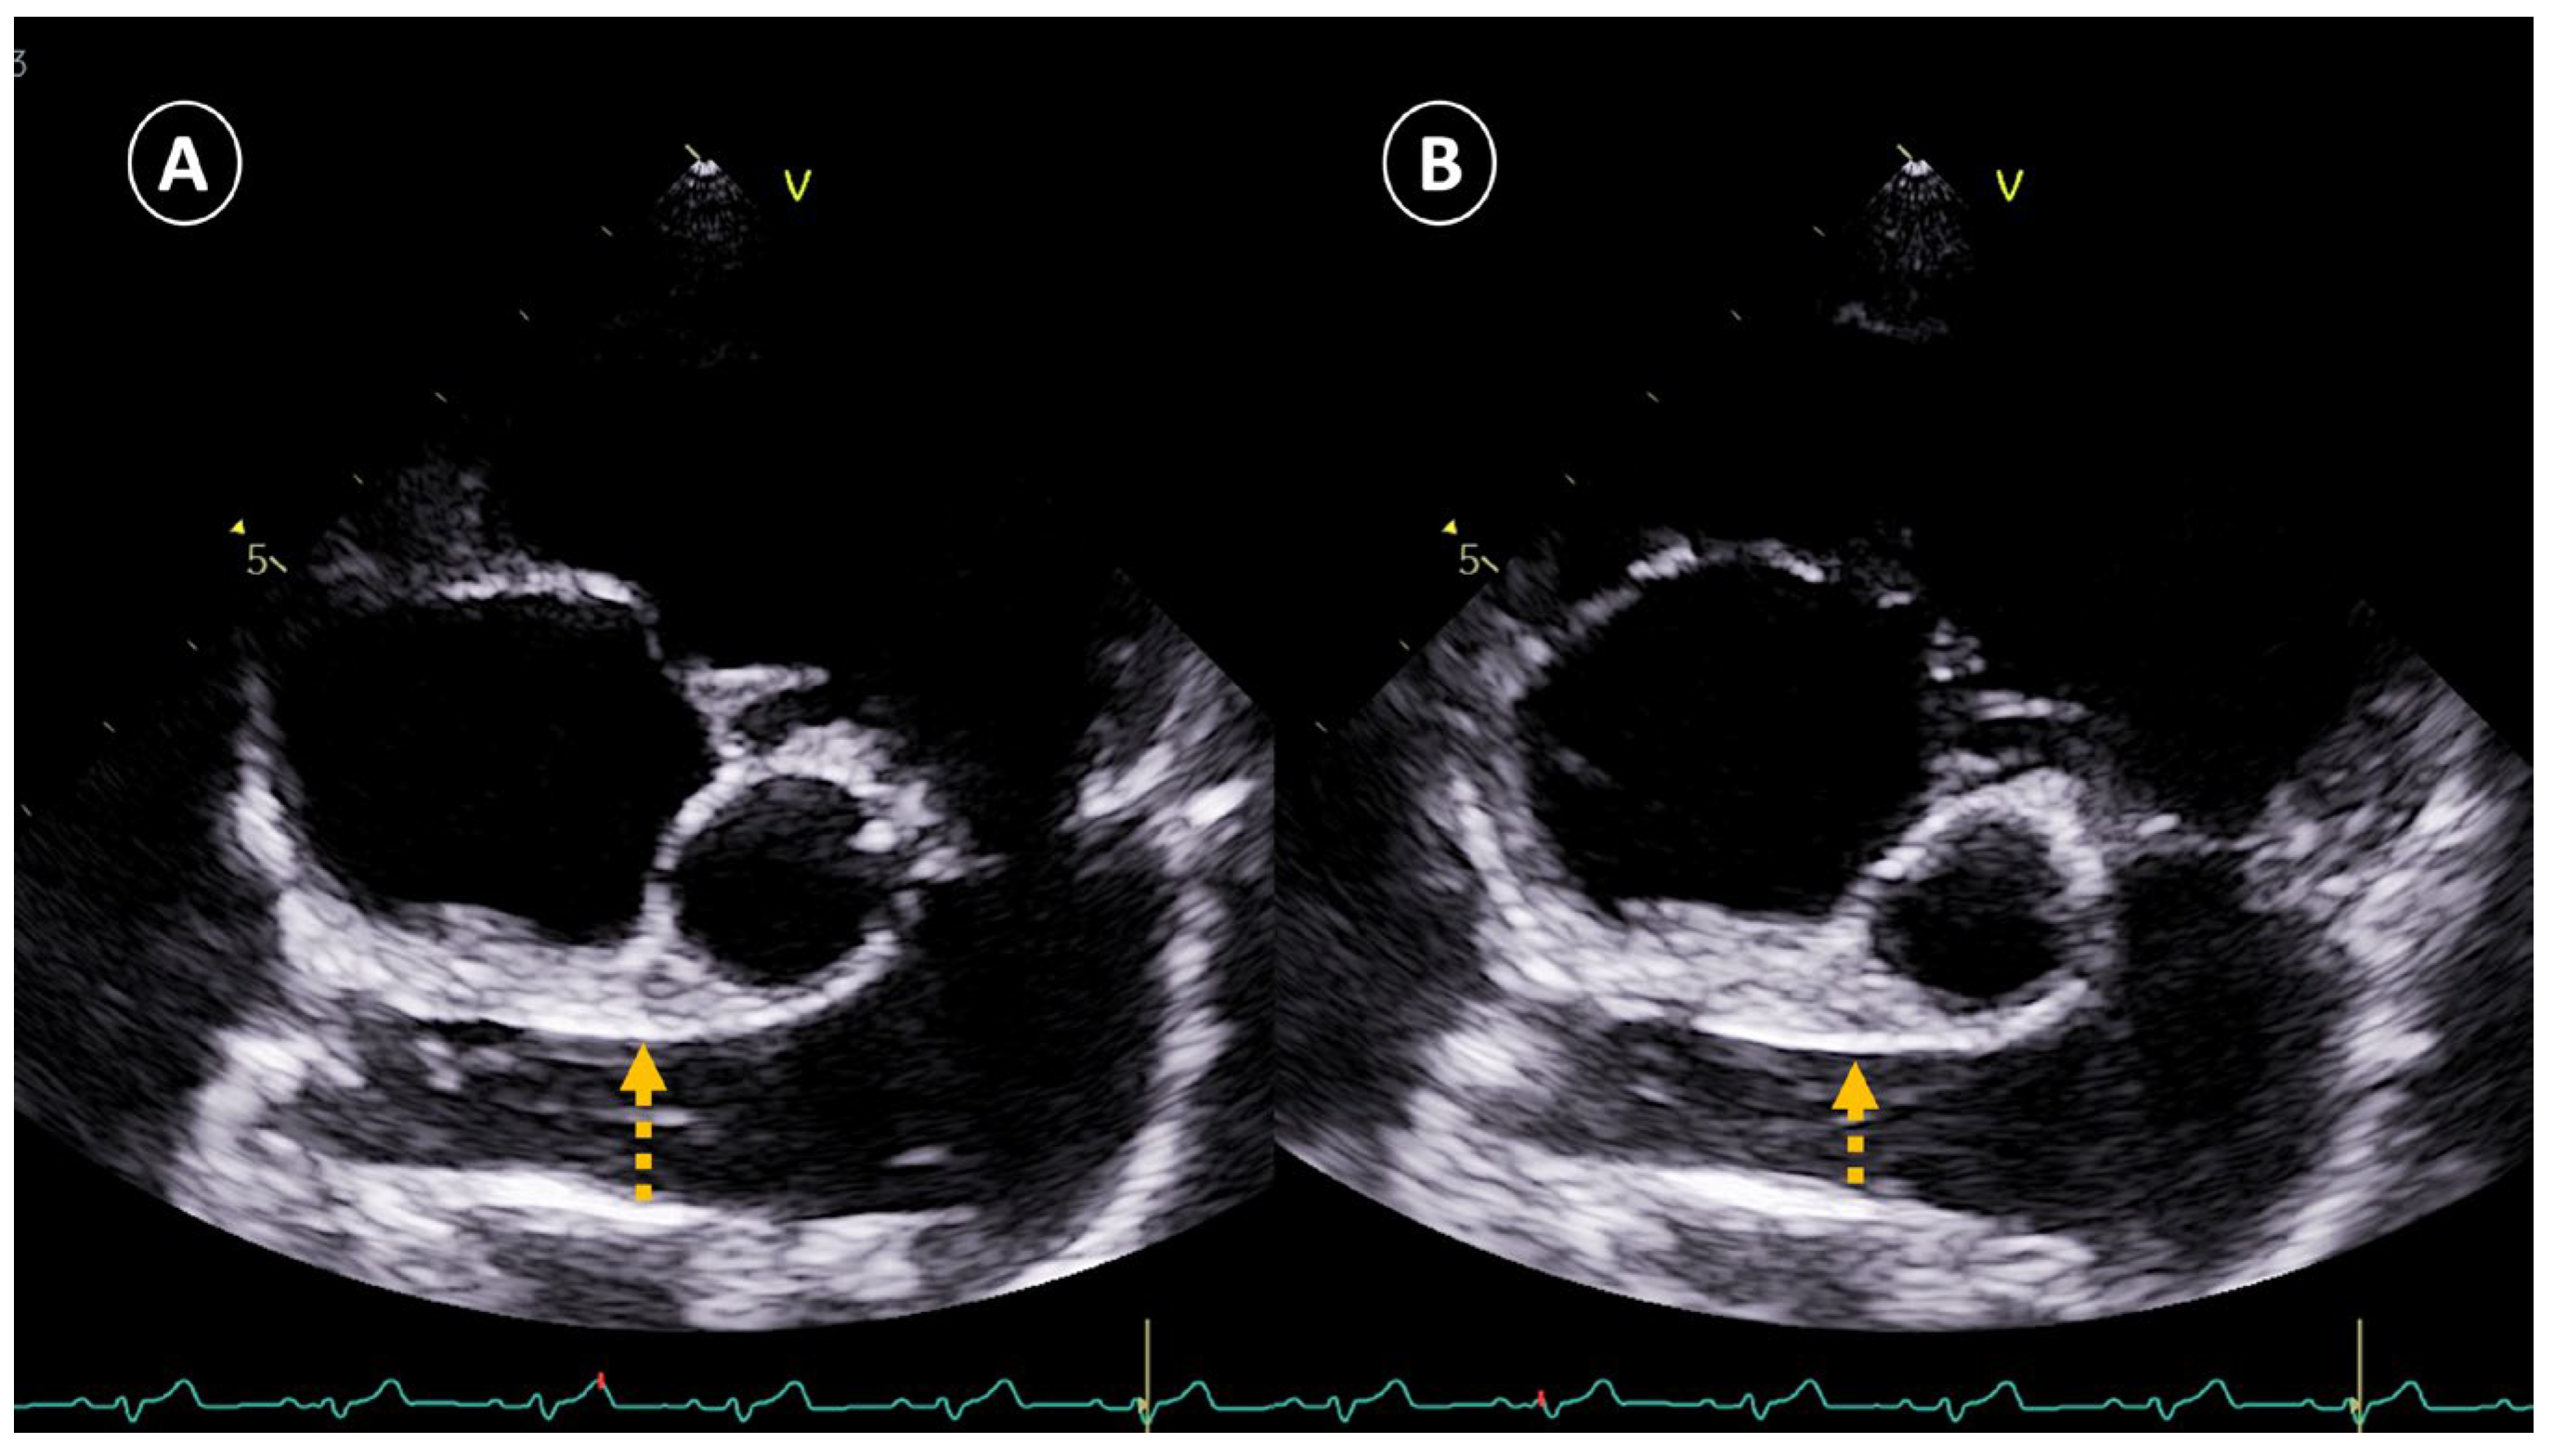

- Echocardiography